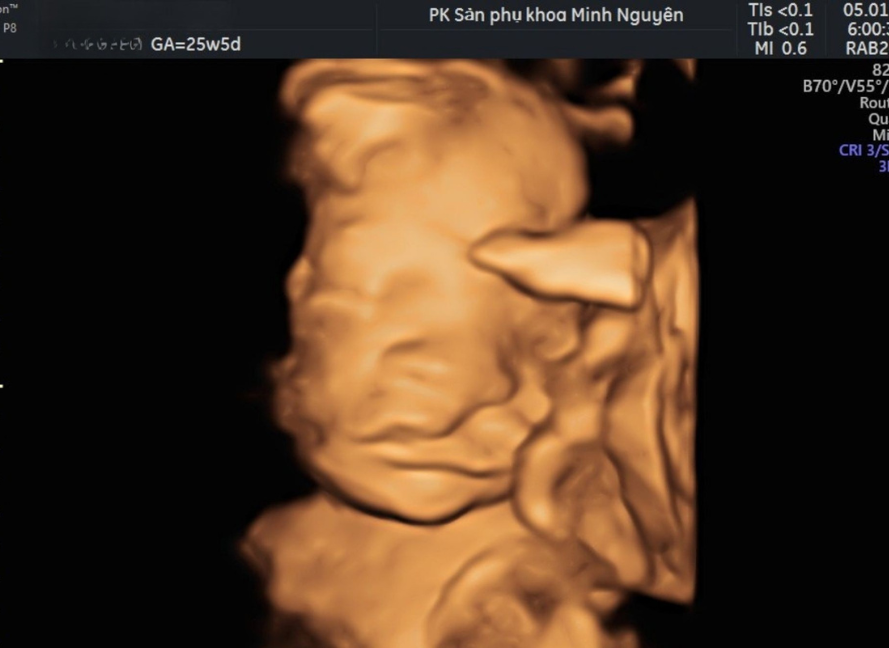

Chị H. đến phòng khám Dr Tú y học bào thai khi thai đã sang tuần 26. Trước đó một tuần, chị được thông báo trên siêu âm hình thái rằng thai có dấu hiệu sứt môi. Kết quả không kèm bất thường nào khác, nhưng chỉ một cụm từ đó cũng đủ khiến chị mất ngủ nhiều đêm.

Bác sĩ Tú không trả lời ngay. Bác sĩ mở lại hình ảnh siêu âm, xác nhận đây là nghi ngờ sứt môi đơn độc, không thấy dấu hiệu hở hàm ếch hay bất thường cơ quan khác, rồi mới bắt đầu giải thích từng bước.

Phát hiện sứt môi trên siêu âm có biết trước được khả năng phẫu thuật không?

Siêu âm thai chỉ đánh giá được hình thái, không đánh giá khả năng phẫu thuật hay kết quả thẩm mỹ sau này. Khi thấy sứt môi trên siêu âm, bác sĩ cần làm rõ các điểm sau:

• Sứt môi một bên hay hai bên

• Khe hở lớn hay nhỏ

• Có nghi ngờ hở hàm ếch kèm theo không

• Có bất thường nào khác đi kèm không

Nếu sứt môi là đơn độc, không kèm hở hàm ếch và không nằm trong hội chứng di truyền, thì khả năng phẫu thuật thành công sau sinh là rất cao.